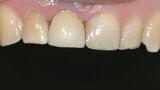

Fig. 18: There was perfect adaptation of the soft tissue around the implant restoration. In addition, a ceramic crown

was placed on tooth #12 (after root canal therapy) and ceramic veneers on teeth #21 and 22. Three years follow up shows stability of soft and hard tissue.